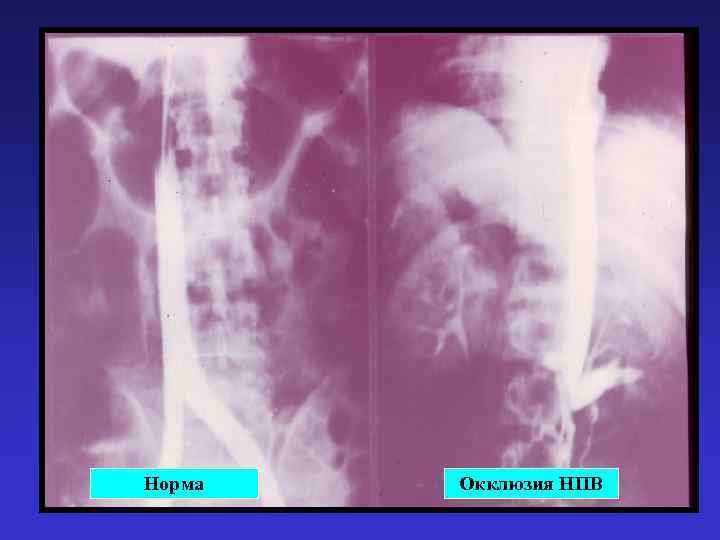

Норма Окклюзия НПВ